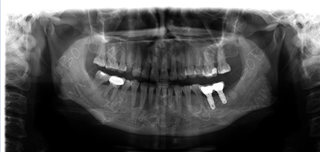

种植牙后口腔内全景片